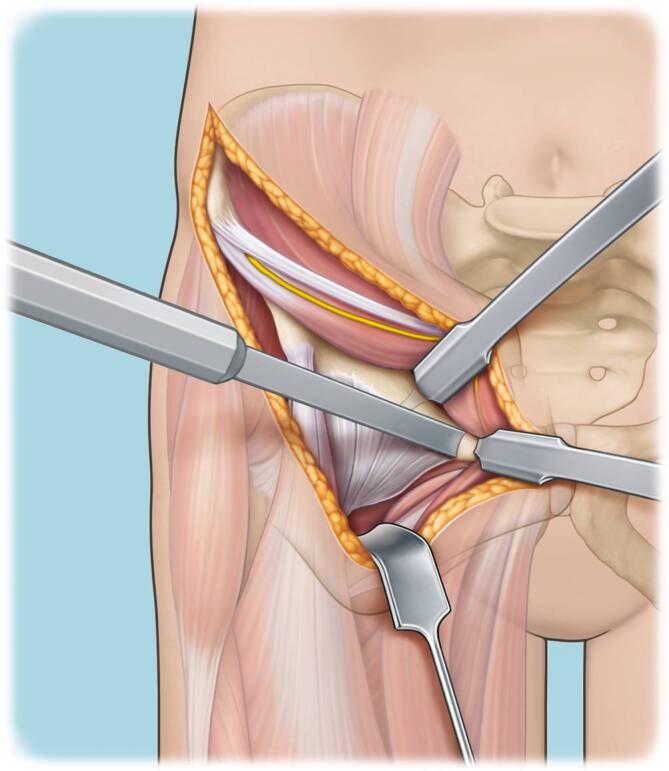

Die ursprüngliche chirurgische Technik der PAO war mit einer ausgedehnten Hautinzision und mit der Ablösung verschiedener Muskelursprünge (vollständig des M. sartorius, des M. rectus femoris und anteilig des M. obliquus internus abdominis, des M. transversus abdominis, M. tensor fasciae latae, der Mm. glutei medius und minimus) assoziiert [3]. Diese Technik wurde über die letzten Dekaden von der erstbeschreibenden Berner Arbeitsgruppe modifiziert [1]. So ermöglichen minimal-invasive Techniken (MIS-PAO) kürzere Hautschnitte und/oder günstigere Inzisionsverläufe, eine reduzierte Ablösung oder den Erhalt der Muskelansätze [13] und somit die Minimierung des Weichteiltraumas, was potenziell zu einer schnelleren postoperativen Genesung des Patienten beitragen könnte [2, 6, 17, 18].

Verglichen mit der konventionellen PAO und den bisher publizierten minimal-invasiven Techniken zeigt die hier beschriebene Technik einige Unterschiede. So wird in der hier beschriebenen Technik ein Bikini-Hautschnitt verwendet und der M. sartorius wird weder abgelöst noch gespalten. Bei der konventionellen PAO wird traditionell der modifizierte Smith-Petersen-Zugang verwendet [7]. Bestandteil der von uns modifizierten, minimal-invasiven PAO-Technik ist ein Bikini-Hautschnitt, ähnlich der Schnittführung des ilioinguinalen Zugangs, welcher parallel zu den Hautspannungslinien verläuft und daher zu günstigeren kosmetischen Ergebnissen führt. Die aktuellen in der Literatur beschriebenen MIS-PAOs verwenden eine den M. rectus femoris erhaltende Technik, wobei der Ursprung dieses Muskels an der Spina iliaca anterior inferior geschont wird [2, 18].

In der hier vorgestellten MIS-PAO-Technik werden sowohl der Ursprung des M. rectus femoris als auch der Ursprung des M. sartorius geschont. Der M. sartorius wird nicht gespalten, sondern in seiner muskulären Integrität erhalten und für den Zugang zu den Osteotomieebenen am Sitzbein und Schambein nach medial mobilisiert.

Minimal-invasive Durchführung einer PAO unter maximal muskelschonender Präparation, ohne Ablösung der Ansätze der Mm. sartorius und rectus femoris.